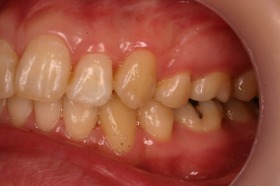

歯の矯正治療 症例ビフォー&アフター

ご覧の症例は出っ歯を矯正治療でキレイにしたケースです。

よく出っ歯は日本人に多いようなイメージがありますが

、世界的に見ても受け口と比較して出っ歯は多いようです。

このような場合では歯を抜いて矯正するか

、抜かずに矯正するか分かれるケースです。

ご覧の矯正歯科治療の場合は、抜いて矯正歯科

治療していますが東京世田谷矯正歯科センターでは

非抜歯矯正歯科治療をベースにしています。

どうしても抜かないとキレイにならない場合のみ

抜歯して矯正歯科治療しています。